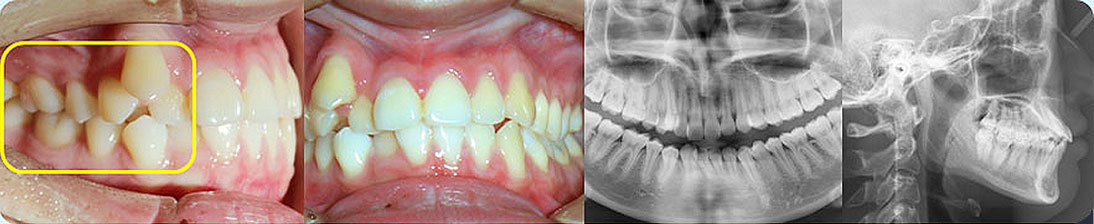

骨性I類,均角,安氏I類

上牙列重度擁擠,下牙列輕-中度擁擠

上中線右偏

13唇側錯位

• 【治療方案】

拔除14,排齊上牙列

下頜尖牙適當擴弓,配合適量鄰面去釉,排齊下牙列

上頜左側配合適量鄰面去釉,調整中線

盡量調整后牙為尖窩咬合關系

矯治前后對比

蛻變周期:上頜16個月,矯治效率提升30%,下頜12個月,矯治效率提升20%